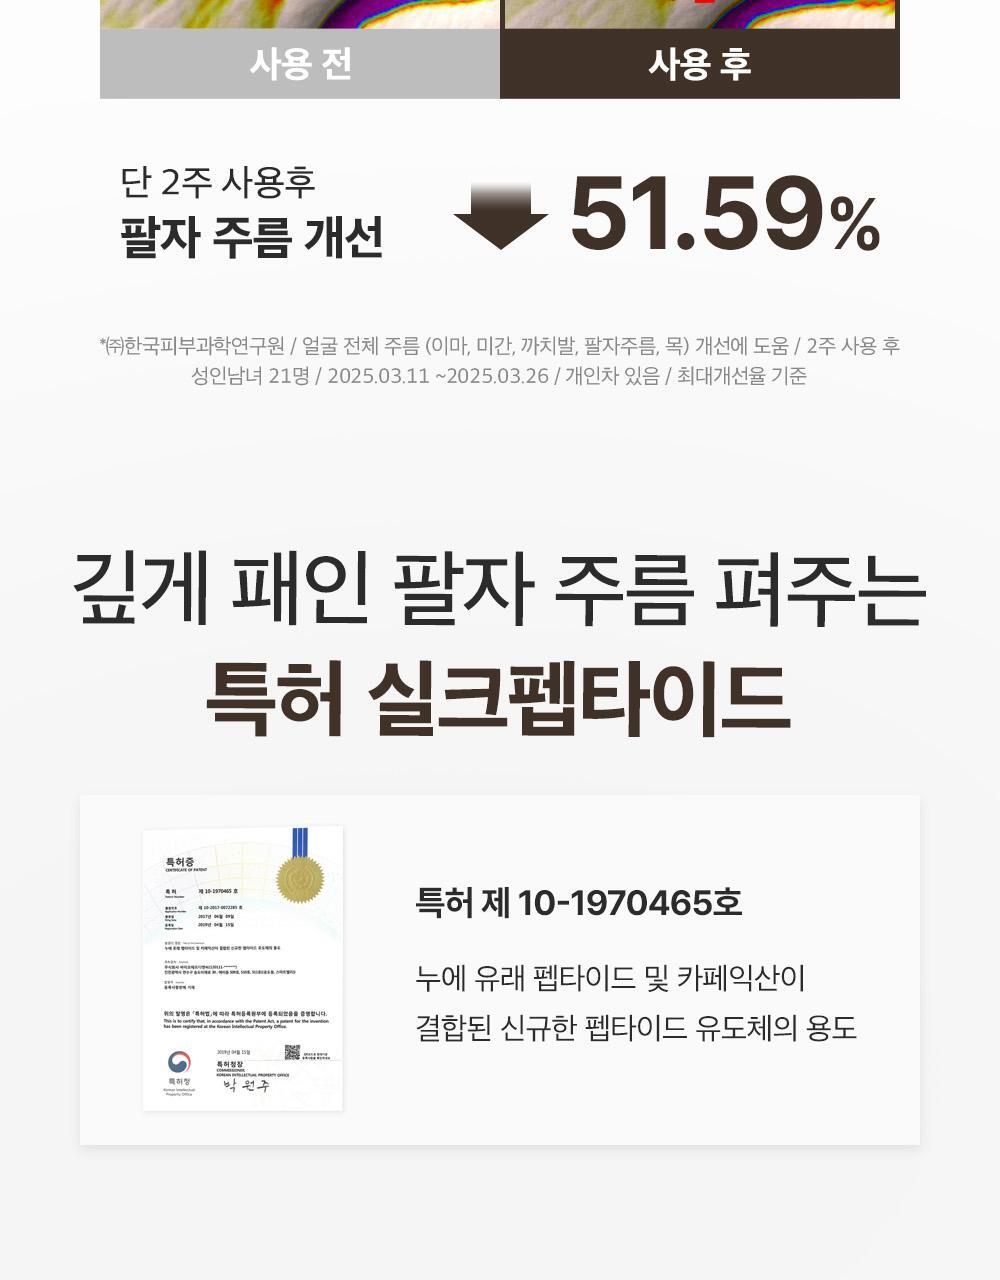

- 30種勝肽複合物提拉護理成分,含專利絲肽,可撫平皺紋

- 已完成人體應用測試。單次使用即可感到提拉緊緻效果。而且這不是暫時的效果。 24小時持續提升力量。持續用更見效果。

成效數據

嘴角凹陷處提升率:56.73%

- 即時效果──「2週持續使用」看得見的改變。